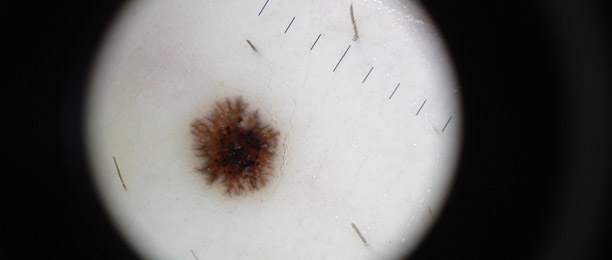

Lo studio e la diagnosi delle neoformazioni cutanee attraverso strumenti specifici indicati per un'analisi delle caratteristiche strutturali superficiali e profonde delle varie neoformazioni cutanee: dermatoscopia, dermalite a luci fotocromatiche, mappatura nevica con videodermatoscopia digitale.

Al fine di una corretta diagnosi dei nevi, e dunque di un'efficace prevenzione da forme tumorali, è indispensabile visionare in profondità i caratteri di ogni formazione nevica. Ciò è reso possibile dall'utilizzo del dermatoscopio e dalla concomitante mappatura nevica, con l' eventuale rimozione chirurgica o laser di: